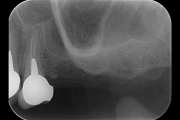

Grande rialzo seno mascellare